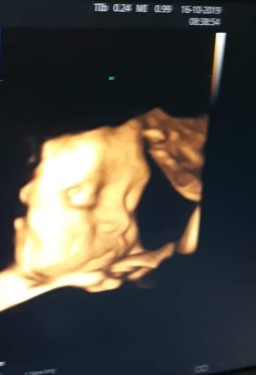

บ้านไหนแตกธันวาคม ขอดูตัวแสบแต่ละบ้านหน่อย บ้านนี้จมูกพุ้งมาเลย? กำหนดคลอด 21/12/62 #หญิง